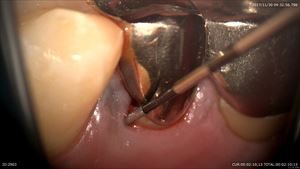

さて一人目のマイクロスコープは診断に使用した方です。

この患者さんはメンテナンス時に衛生士から見て欲しいといわれました。

被せ物が合っていないだけではなくヒビ?があります。

マイクロスコープにて歯根の上部が破折と診断。画像と線で患者さまに説明

細菌感染が根管の外まで広がっています。治療の計画を詳しく説明

納得して帰られました。抜きません。丁寧に次回から保存治療です!